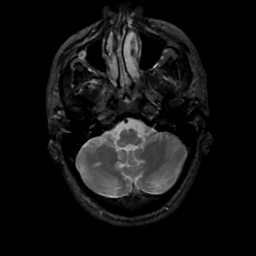

MR Study #2, February 17, 1991 -- Slice #9

[Home][Help][Clinical][Tour 1][Tour 2] Slice 9